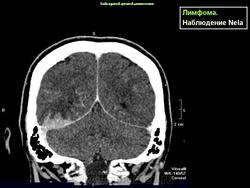

Лимфома.

Лимфома задней черепной ямки